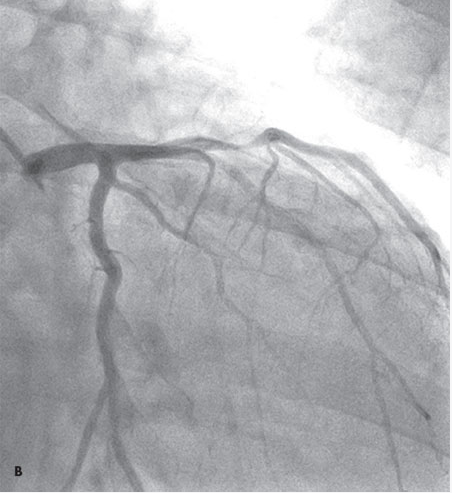

Coronary arteriography revealed single-vessel disease with a 90% stenosis of the proximal left anterior descending (LAD) artery (B). Ejection fraction was 50%. The patient received a drug-eluting stent to the LAD artery lesion and was discharged home the following day in good condition.